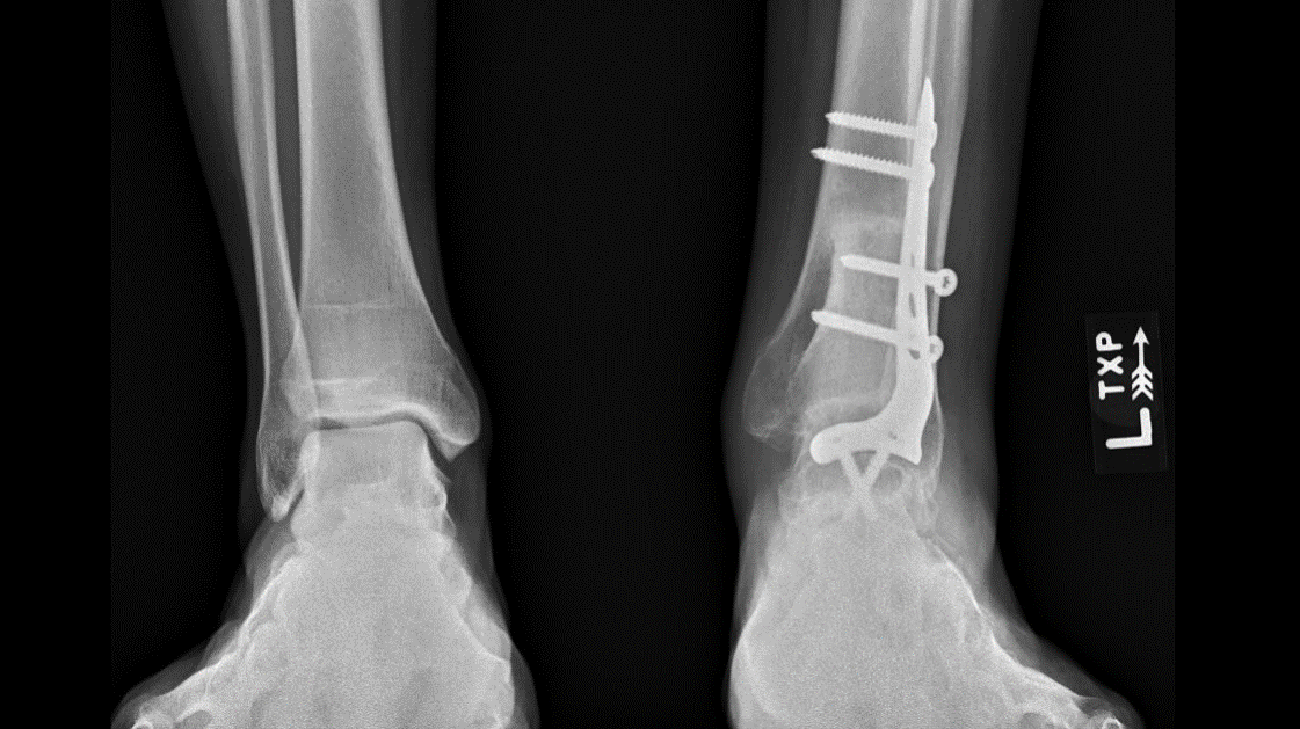

Once the first seven cycles of chemo were complete, it was time for the surgery to remove the cancer. To do this, Dr. Nystrom used MRI and CT scans of John Paul’s ankle region to create custom cutting guides that match exactly to the contour of his bone. Another set of guides was made to match the donor bone.

Armed with this patient-specific instrumentation, Dr. Nystrom carefully removed the cancerous bone and also cut an identical piece to replace it out of the donor bone. “It’s a very precise method,” explains Dr. Nystrom, “so the ‘new’ replacement bone fit into John Paul’s tibia like the last piece of a puzzle.”

Because the surgical area was where the ankle meets the tibia, Dr. Nystrom also had to fuse John Paul’s ankle to the tibia, which limits the ankle area’s overall movement by about 50%. However, it was a necessary step to keep it sturdy enough to endure walking and running.